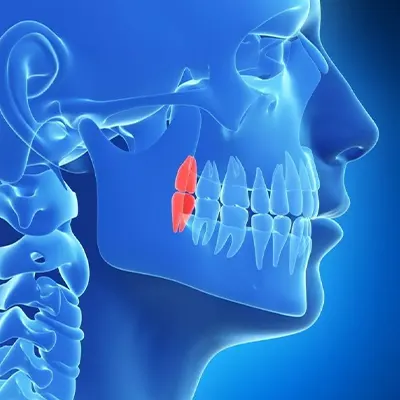

Chowdhury’s Premium Dental offers advanced X-ray services for accurate diagnoses and personalized treatment plans. Our state-of-the-art digital X-ray technology detects hidden issues, enabling us to assess oral health conditions and deliver precise care. Trust our expertise and the latest techniques for comprehensive, efficient dental services tailored to your well-being.